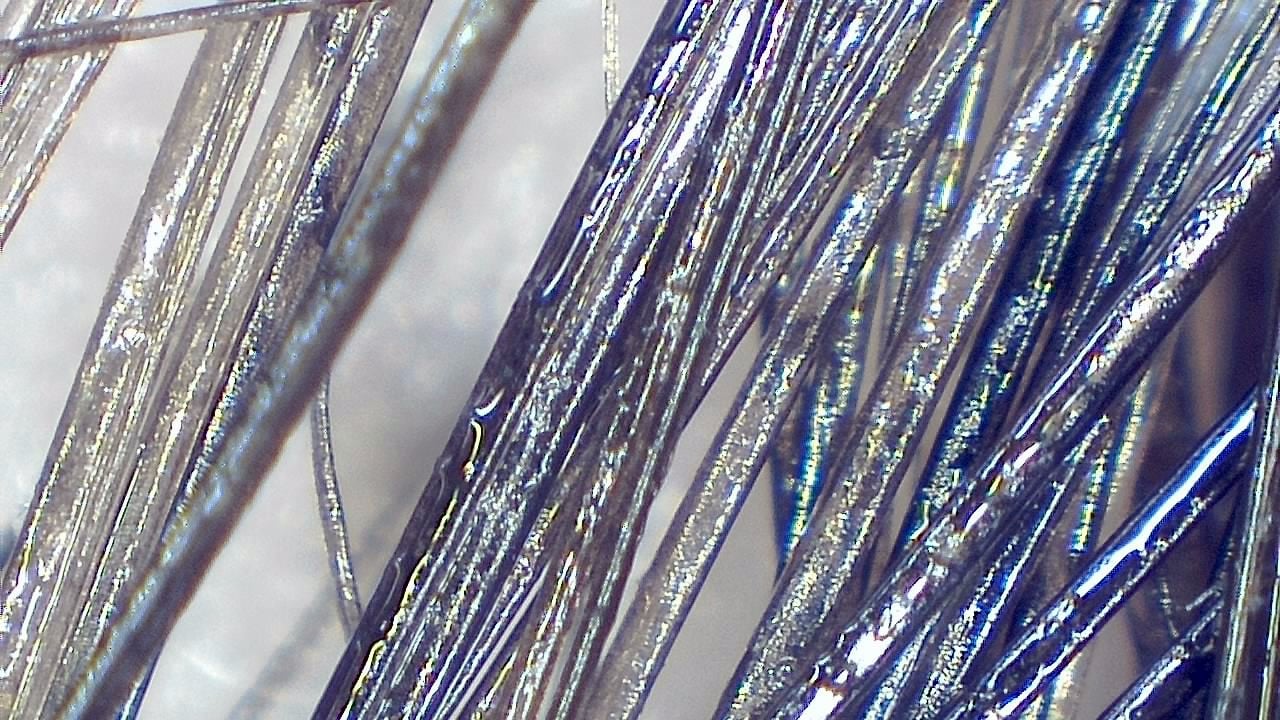

Trichoscopy is a non-invasive diagnostic technique that enables detailed evaluation of the scalp and hair shaft. Smart G-Scope provides the magnification and resolution needed to identify characteristic signs of different types of alopecia.

It is possible to visualize yellow dots, vellus hairs, follicular miniaturization, and other key dermoscopic markers used in the differential diagnosis of androgenetic alopecia, alopecia areata, and scarring alopecias.

- Visual estimation of follicular density and hair shaft thickness

- High-quality images for reports and patient communication